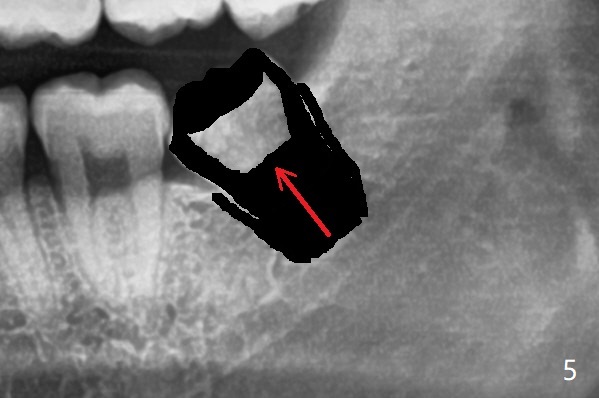

牙根容易取出(图六:箭头),不易损伤下面神经。